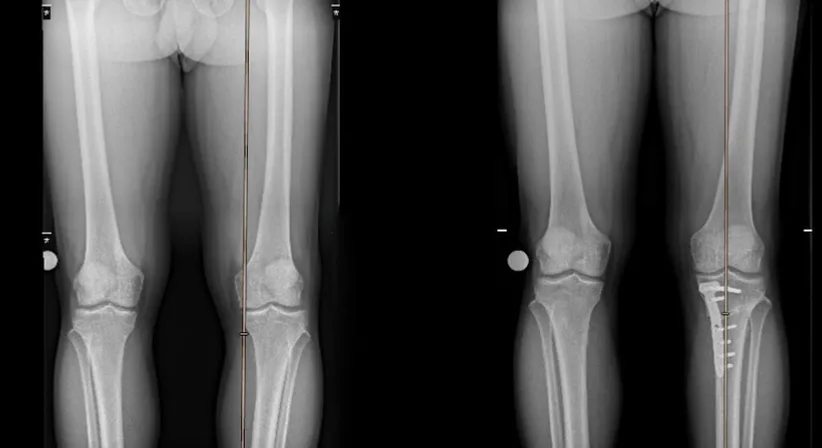

Beinachsenkorrektur bei X- und O-Bein Fehlstellungen

Beinachsenabweichungen bedingen häufig eine verfrühte Abnutzung eines Kniegelenkanteils, bei O-Beinen (Genu varum) der Gelenkinnenseite und bei X-Beinen (Genu valgum) der Gelenkaußenseite. Außerdem können hohe Achsabweichungen auch zu Instabilitäten im Kniegelenk führen.

Häufig können die Beinachsenkorrekturen mit Knorpel oder Meniskustherapien kombiniert werden, was auch sinnvoll ist. Wichtig ist, dass die knöcherne Korrektur dort durchgeführt wird, wo auch der Fehler im Knochen ist. Das bedeutet, dass manchmal auch zwei Knochenosteotomien zur Korrektur einer Achsfehlstellung notwendig sind, da sowohl im Oberschenkel als auch im Unterschenkel ein relevanter Knochenfehler besteht. Voraussetzung zum Erkennen dieser knöchernen Fehlstellungen ist deshalb eine sehr genaue und sorgfältige präoperative digitale Planung am Röntgenbild. Daraus errechnet sich auch die während der Operation durchzuführende Korrektur. Ohne eine derartige Planung wird jede Art von Umstellungs-Osteotomie scheitern.